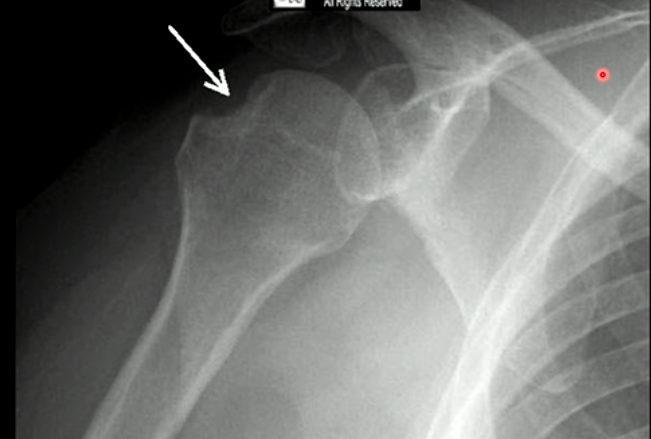

How would you diagnose this image?

Hill-Sachs Deformity

What can cause Hill Sachs deformity?

Repetitive anterior dislocation of the humerus. 50% to occur on the first dislocation, but becomes more likely as the humerus is dislocated more times